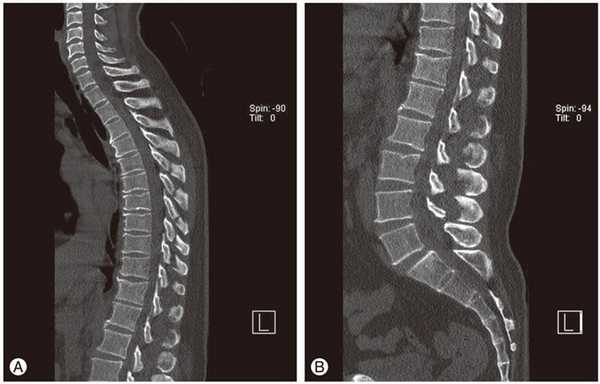

- рентгенография и компьютерная томография: эффективны лишь на поздних стадиях развития заболевания, когда изменения становятся хорошо заметными;

- рентгенография. Наиболее информативна при шейно-грудном остеохондрозе. На полученных изображениях заметны деформированные позвонки, уменьшение промежутков между ними, образовавшиеся костные наросты;

- МРТ или КТ. Проведение исследований позволяет обнаружить изменения межпозвонковых дисков, оценить состояние связок, мышц, кровеносных сосудов, спинномозговых корешков.